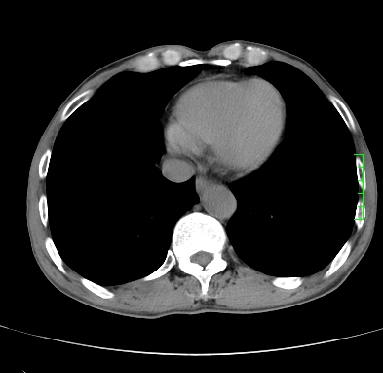

m,73y。膝关节疼痛伴双下肢水肿。入院常规胸片发现结节灶。增强为静脉期。

浅分叶、棘突,考虑右下肺周围型肺癌

考虑周围型肺癌  ,双上肺结核。

肿块周围可见局限性气肿,考虑肺癌可能性大。双肺上叶继发型肺结核。

指套征,强化明显,近侧肺组织局限性肺气肿,考虑支气管类癌,慢支、肺气肿、双上陈旧性tb、冠脉钙化。

1)考虑右肺下叶周围型肺癌。2)右肺上叶及左肺感染性病变(结核可能)。3)肺气肿。4)冠状动脉钙化。